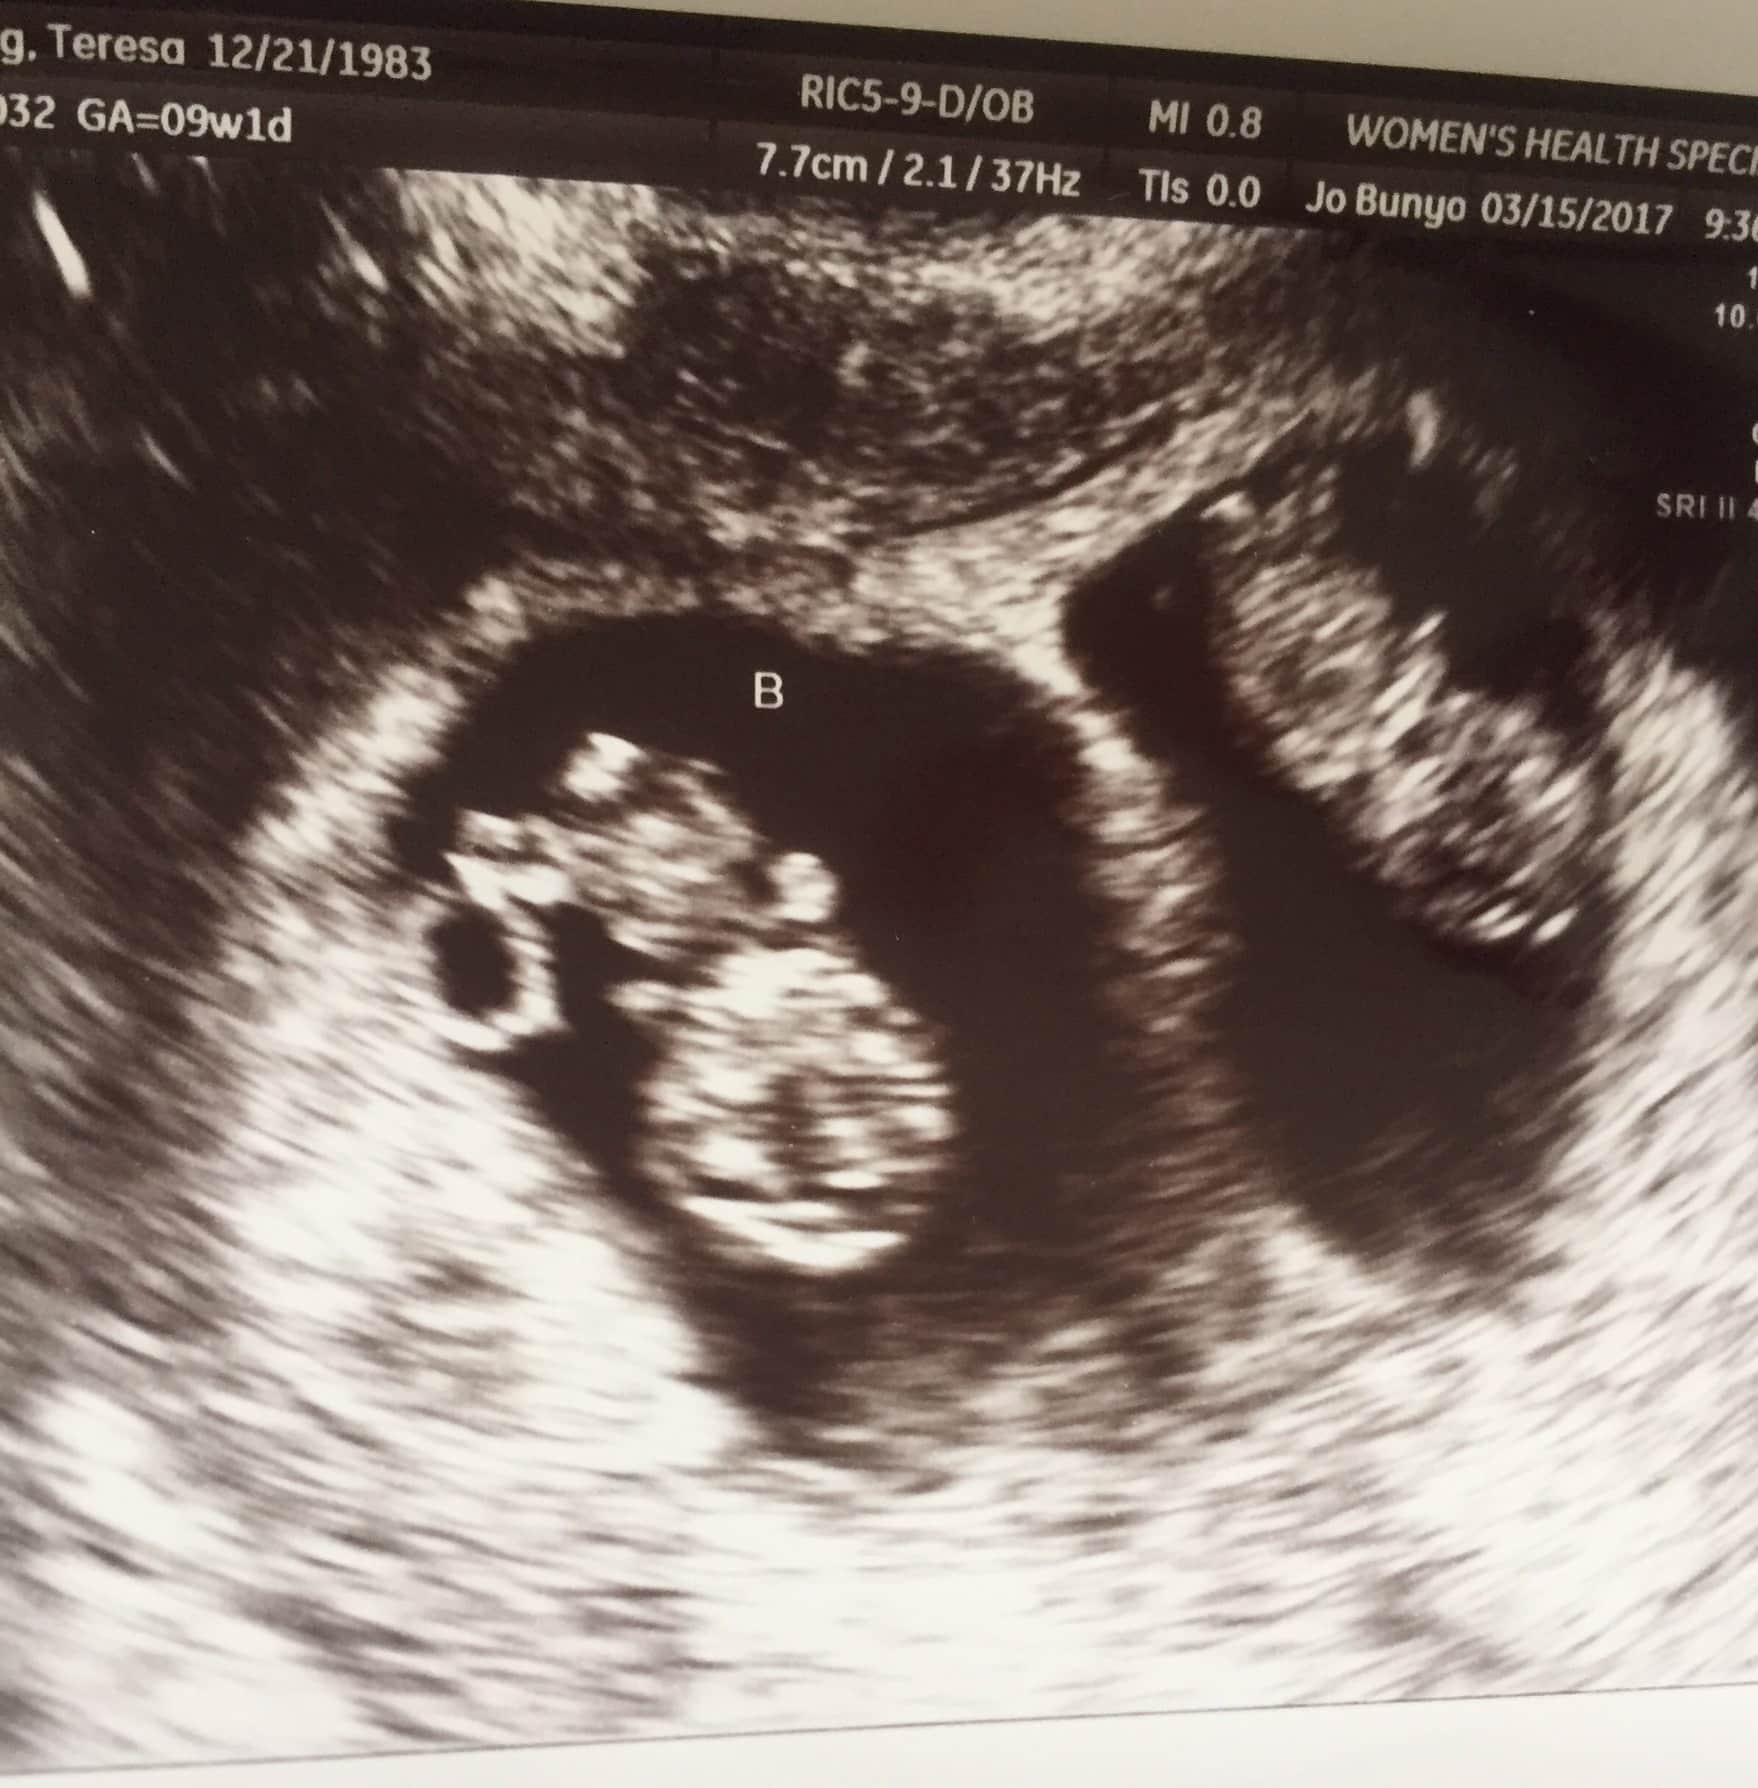

Ultrasound Photos at 12 Weeks Pregnant With Twins